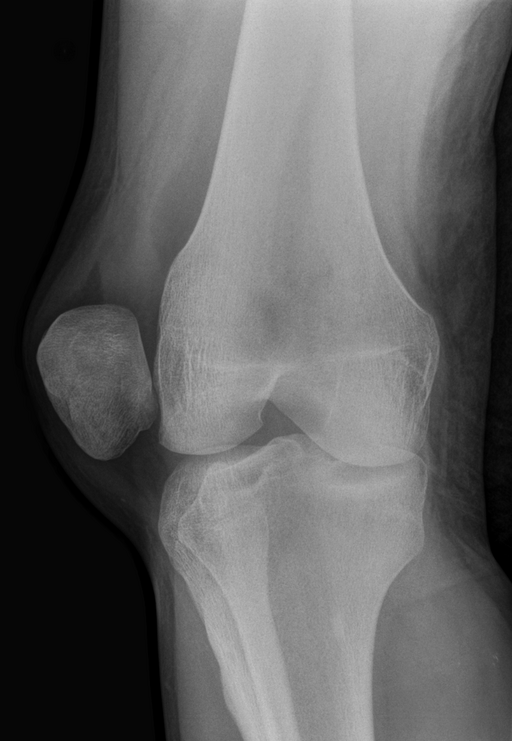

Radiografie care arată luxația rotulei la nivelul genunchiului

Investigații imagistice

Pentru confirmarea diagnosticului și identificarea leziunilor asociate pot fi recomandate:

• radiografia genunchiului

• RMN-ul genunchiului

• uneori CT-ul genunchiului

RMN-ul permite evaluarea ligamentelor, cartilajului și a altor structuri ale genunchiulu